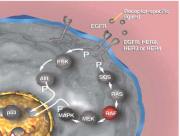

| 17:27, 11 באוגוסט 2014 | BCC-SMO.png (קובץ) |  |

326 קילו־בייטים | Motyk | 1 | |